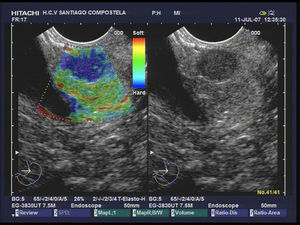

La elastografía es un nuevo desarrollo que utiliza la técnica de ultrasonido para proporcionar una estimación de la rigidez del tejido, midiendo el grado de distorsión en virtud de la aplicación de una fuerza externa. Esta técnica se está empleando ya para el diagnóstico diferencial de lesiones pancreáticas destacando en líneas generales la mayor dureza (patrón heterogéneo de predominio azul) de las lesiones tumorales frente a las lesiones inflamatorias (color verde). Destaca que los TNE malignos mediante el estudio elastrográfico muestran un patrón homogeneo azul29 (fig. 4). En la actualidad se puede realizar un estudio elastográfico cuantitativo, mostrando los TNE los valores más altos en el coeficiente de elasticidad30 (fig. 5).